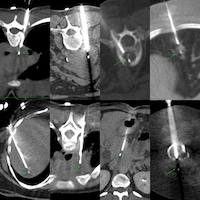

Case 114: Pulmonary Arteriovenous Malformation (PAVM)

A 55-years old with carcinoma endometrium was referred for an opinion for a lung nodule diagnosed on the PET/CT.

A closer look showed linear vessels leading up to the nodule and MIP images showed a classic AVM.

The video discusses the case and the current knowledge base of PAVMs along with other similar cases